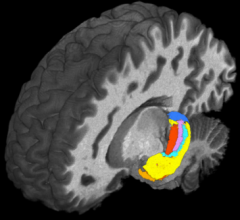

November 11, 2021 — Transcranial focused ultrasound can be used to treat degenerative movement disorders, intractable ...